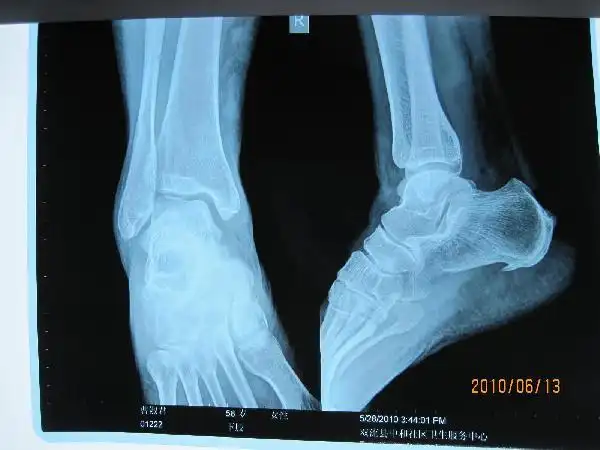

足跟骨骨刺怎么治疗?

疾病真相你所不知道的骨刺的秘密